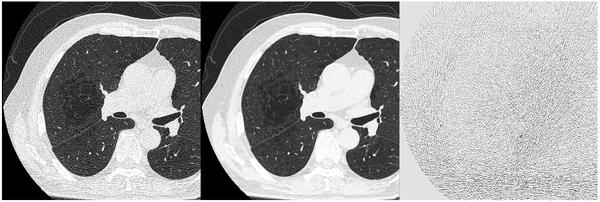

従来の逐次近似処理では,処理後の画像ボケやコントラスト低下などを理由に,撮影線量を十分に下げられないなどの課題があった。そこで,さらなる低被ばく化をめざして,Deep Learningを設計段階で用いて画像再構成技術DLR Focusを開発した。DLR Focusは,低線量撮影したノイズの多い画像に対して,構造を維持したままノイズを低減する*8。

DLR Focus(左:処理前 中:処理後 右:処理前後の差分)

処理前後の差分画像から,断面の構造を保ったままノイズだけが除去されていることが分かる。